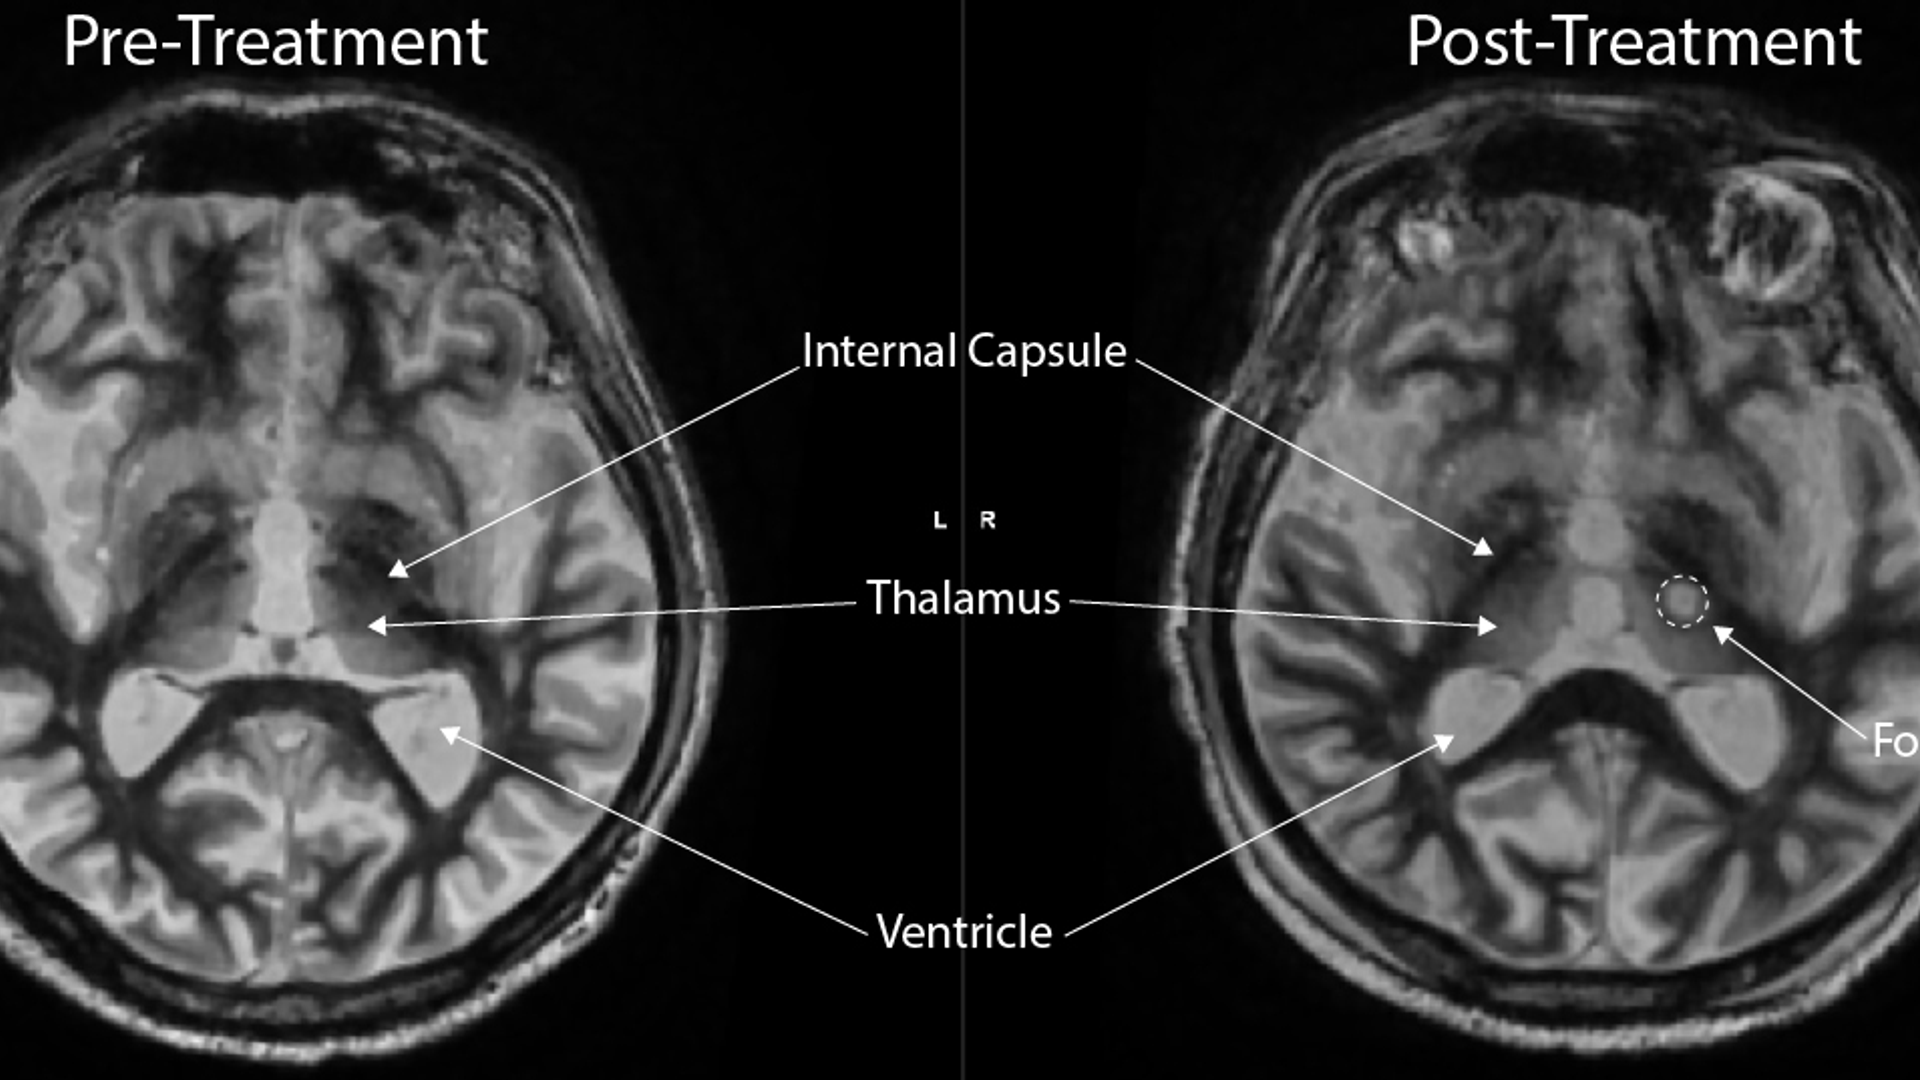

MRI scans of pre- and post-treatment

Figure 2: Pre- and Post-Fast Gray Matter Acquisition T1 Inversion Recovery (FGATIR) 3T MRI demonstrating thalamic VIM tremor source (left panel) and post-treatment left-sided focused ultrasound lesion (right panel).

After treatment, the Mr M had a physical therapy evaluation and was discharged home in the early afternoon. A post-treatment MRI performed prior to discharge (Figure 2) confirmed a lesion within the ventral intermediate nucleus of the thalamus.